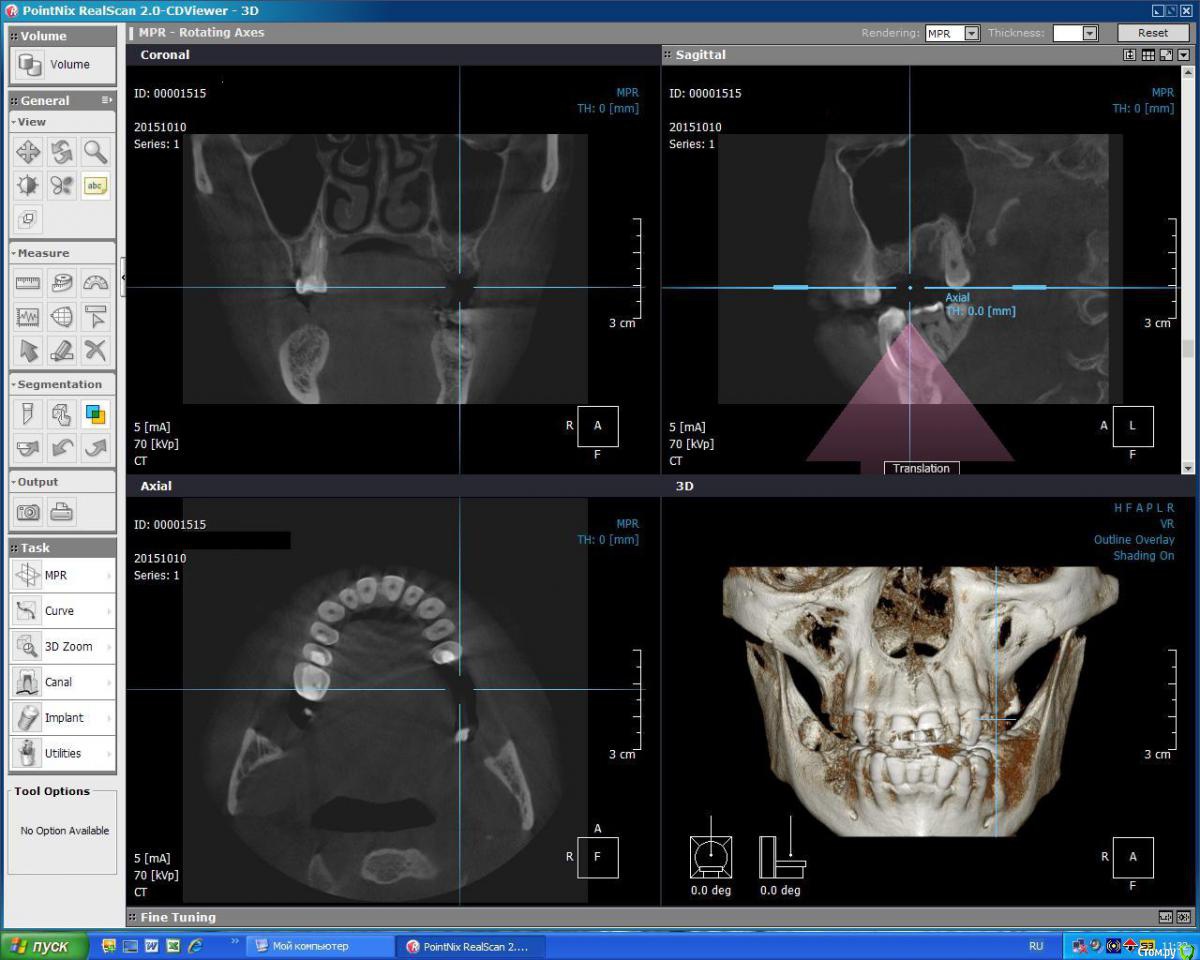

kuznetsovaev Опубликовано 19 октября, 2015 Поделиться Опубликовано 19 октября, 2015 (изменено) Добрый вечер, уважаемые врачи, подскажите мне пожалуйста какой вариант имплантации более правильный. Буду очень надеяться на вашу помощь. Так же буду рада если будут еще какие-то может более верные варианты. Заранее благодарю. Были кисты на верхней и нижней челюсти, в связи с чем удалили зубы.КТ от 10.10.2015г. Мне 33, пол женский.Верх лево: 7зуб и киста над ним удалены 18.09.2015, соседний 6-ой удален 3года назад.Низ право: 6-ой зуб удален 20.04.2015, киста и 7-8 зубы удалены 13.08.2015г. Пока хожу по клиникам ищу "своего" врача и слышу разные мнения. Вариант 1.1. Нижние 6 и 7 импланты ставить без костной пластики через пару месяцев (в декабре), кость сама нарастет. Сделать прицельный снимок перед имплантацией и все, т.к. очертания кости уже видны, кость просто станет более плотной, а границы уже не изменятся.2. Верхние 6 и 7 ставить через полгода после синуслифтинга. Вариант 2.1. Нижний 6 без костн.пластики, а в 7 лунку пересадить свой костный материал закрепив минигвоздиками (если правильно запомнила). Спустя три месяца ставить импланты сразу в 6 и 7.2. Верх синуслифтинг над 6 и 7кой, через полгода ставить и 6 и 7 имплантат. В этом варианте прозвучала еще мембрана и 4 болтика, я не поняла куда ее крепить будут. Вариант 3.1. Низ 6 готова к имплантации, а в 7ку засыпать микс кости моей и инородной. Спустя два-три месяца ставить импланты сразу в 6 и 7.2. А на верхней челюсти над 6-ой подъем пазухи, а над 7-кой не надо поднимать, а нужно засыпать в ее лунку смесь моей и инородной кости, закрыть мембраной. Ну и через полгода имплантация. Вариант 4.1. Внизу без костной пластики.2. Верх через закрытый синус досыпят кости с одновременной имплантацией. Изменено 19 октября, 2015 пользователем kuznetsovaev Ссылка на комментарий

kuznetsovaev Опубликовано 21 октября, 2015 Автор Поделиться Опубликовано 21 октября, 2015 Доброго дня всем, видимо кроме меня(Сегодня в клинике где делала ОПТГ решила проконсультироваться и на счет имплантов.Где меня ортопед и хирург ошарашили новой для меня негативной информацией:1. У меня неправильный прикус. (Я не знала этого.)2. Щелкает челюсть при открытии. (Да она действительно иногда хрустит, видимо я к этому так привыкла что не обращала на это внимание.)3. Имплантация возможна только после ортодонтических процедур раздвижения зубов и установки правильного прикуса. Говорят недостаточно места для нормальной высоты коронки.4. Ну и полная санация. Я знаю что есть вторичный кариес на 15,25, 6 и 7 нижние. Ну это мелочи, сейчас этим занимаюсь. Если еще где-то есть все вылечу. Теперь получается что два-три года мне будут двигать зубы и только потом ставить импланты? Убыль кости будет конкретная, уже без костной пластики не обойтись?И что делать с хрустом в суставе - это пройдет после установления правильного прикуса?я очень расстроена( куда мне в моем возрасте носить брекеты... да и дорого этоно если выхода нет то буду носить, если это не "развод" конечно Ссылка на комментарий

faity Опубликовано 21 октября, 2015 Поделиться Опубликовано 21 октября, 2015 удаление 2.8, 3.8брекетычерез год после начала лечения синуслифтинг с имплантацией 2 сегмент(слева сверху)через 4 месяца после синуса имплантация 4 сегмент(снизу справа)снимаем брекетыставим коронки на импланты и на 1.6, 1.5, 2.5, 3.6 после ревизии каналов 1 Ссылка на комментарий